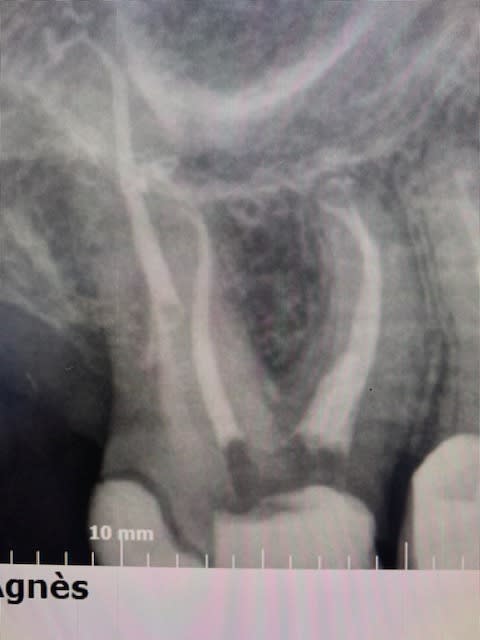

Pas besoin de 40 radios, juste deux.

> Pas besoin de 40 radios, juste deux.

On a compris le doute ne ta bite pas.